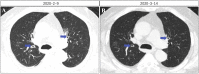

Patients with Coronavirus Disease 2019 (COVID-19) often have clinical characteristics, such as chest tightness and dyspnea. Continuous, unresolved dyspnea often indicates the progression of lung lesions. The mechanism that underlies the chest distress and dyspnea in patients with COVID-19 is still unclear. Chest CT has a higher sensitivity and can play an essential role in the diagnosis and treatment of the disease. However, our clinical observations showed that although some patients had significant chest distress and dyspnea, the lesions that were observed in the lungs during computed tomography were milder and not completely consistent with clinical symptoms. We analyzed the clinical characteristics, laboratory test results, and imaging findings of these patients. We found that extensive inflammation of the bilateral and respiratory bronchioles in patients with COVID-19 due to excessive activation of proinflammatory cytokines and chemotactic aggregation of T-lymphocytes at the site of inflammation are possible mechanisms underlying chest distress and dyspnea in patients with COVID-19. Short-time and lose-dose use of corticosteroid may be helpful to treat chest tightness and dyspnea in mild COVID-19 patients. Through this study, we aimed to improve our understanding of the pathogenesis of COVID-19.